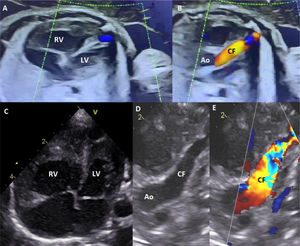

Prenatal and postnatal echocardiograms showing right ventricular dilatation and large coronary fistula. (A) Prenatal 4-chamber view with right ventricular dilatation, compared to the left ventricle. (B) Prenatal view showing a large coronary fistula with antegrade flow from the aorta to the apex of the right ventricle. (C) Postnatal 4-chamber view with right ventricular dilatation. (D and E) Postnatal view showing a large coronary fistula with antegrade flow from the aorta. Ao: aorta; CF: coronary fistula; LV: left ventricle; RV: right ventricle.

A term newborn (38 weeks, 2965 g) was diagnosed prenatally with a large coronary artery fistula (CAF) from the left anterior descending artery to the apex of the right ventricle, causing hemodynamic compromise, including right ventricular dilation and retrograde aortic flow (Figure 1). The delivery was planned to take place at a tertiary center with cardiac assistance. After an uneventful vaginal delivery, the baby was transferred for surgical intervention.

Echocardiography confirmed a large CAF with bidirectional flow and systemic diastolic steal. Computed tomogrpahy angiography (CTA) showed a large, tortuous vessel (8 mm × 7 mm at origin), distal diameter of 6 mm, with significant dilation of the right ventricle and atrium (Figure 2). Surgical ligation of the fistula was performed on day 3 (Figure 2). Persistent fistula on follow-up echo and CTA required re-ligation above the previous site on day 11, which resolved the condition. Both surgeries were uneventful, performed without extracorporeal circulation. The baby was discharged on day 17 with anticongestive therapy and is currently doing well, weighing 4600 g at 2 months.